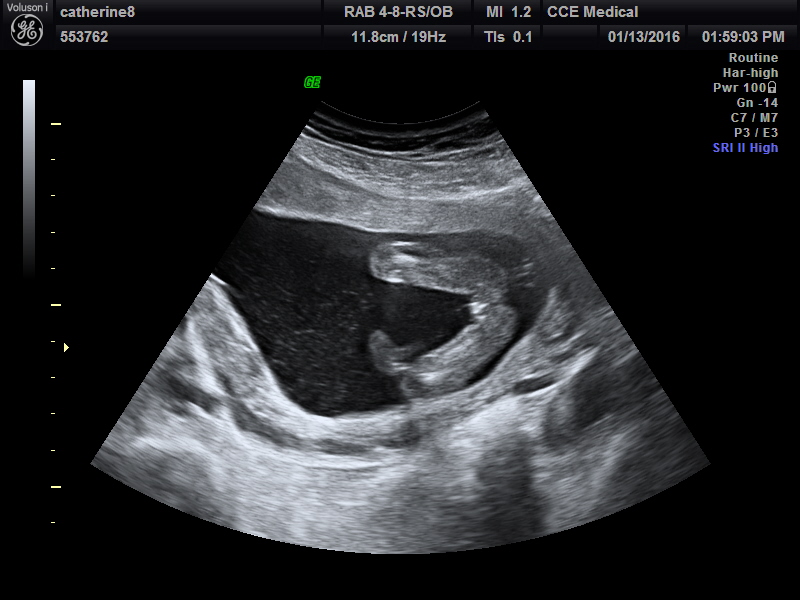

Still a girl! 18 weeks 3 days!

Attachment 29563Attachment 29564